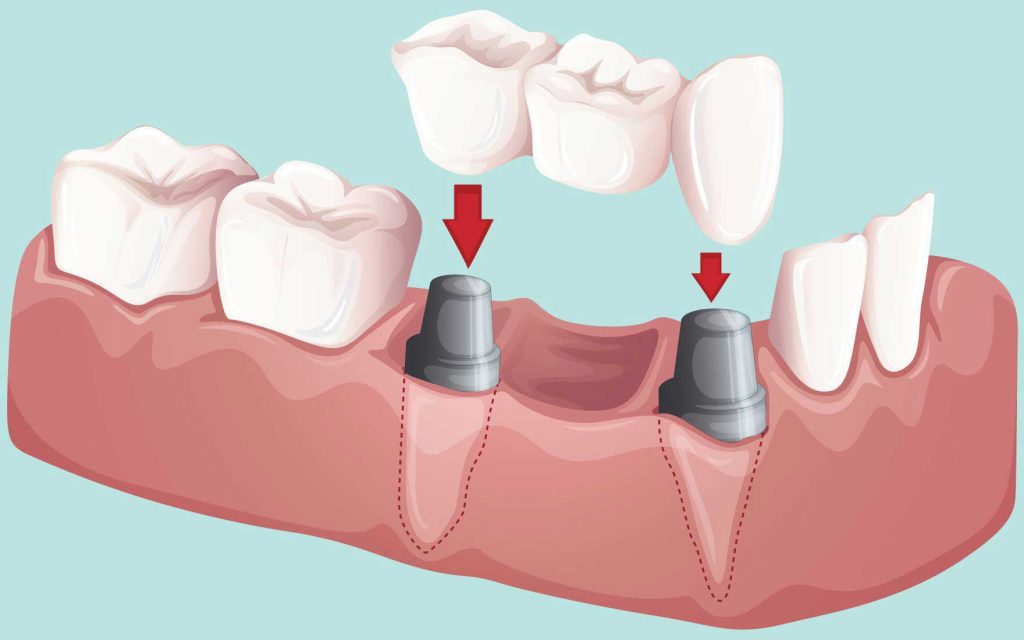

- پلهای دندانی و روکشها

بریج دندان برای جایگزینی دندانهای از دست رفته، خراب یا شکسته بسیار مناسب است. پروستودنتیست پروتز دندان را بین دو روکش دندان قرار میدهد تا پل دندانی تشکیل شود.

زمانی که دندانهای طبیعی نمیتوانند از پروتز دندانی پشتیبانی کنند، از پلهای پشتیبانی شده با ایمپلنت دندان استفاده میشود. پزشک شما از پل دندانی زمانی استفاده میکند که یک یا چند دندان در یک ردیف نداشته باشید. اما این فاصلهها باید بین دو دندان پایه (abutment) باشد. اباتمنت دندان نقش واسطه ای حیاتی بین پایه ایمپلنت کاشته شده در فک و روکش دندان مصنوعی ایفا می کند و پایداری و زیبایی نهایی لبخند شما را تضمین می کند.